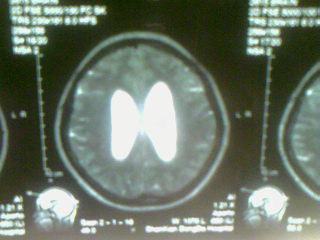

标题: MRI2125:女 45岁 头疼头晕3个月 [打印本页]

标题: MRI2125:女 45岁 头疼头晕3个月

1)考虑第四脑室脉络膜丛乳头状瘤,不排除室管膜瘤。2)阻塞性脑积水。

考虑 第四脑室室管膜瘤或脉络膜丛乳头状瘤伴梗阻性脑积水。

1)考虑第四脑室室管膜瘤,不排除脉络膜丛乳头状瘤。2)阻塞性脑积水。

考虑 第四脑室室管膜瘤或脉络膜丛乳头状瘤伴梗阻性脑积水